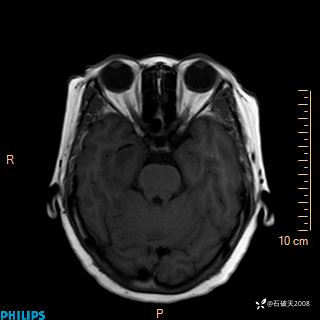

颅内占位,影像征象不是很丰富,有病理

hyy838 推荐女 62岁 主 诉:头晕12小时,加重1小时。

现病史:患者于12小时前无明显诱因出现头晕,呈持续性,无天旋地转及行走不稳,伴恶心、呕吐,呕吐共5次,呕吐物为胃内容物(具体性质不详),无胸闷、胸痛、心慌,无腹痛、腹泻,无咳嗽、咳痰,无发热、意识不清、肢体抽搐及大小便失禁等,1小时前患者上述症状加重,未诊疗,为求进一步治疗急自行来我院,门诊以“头晕待查”为诊断收入我科,发病来,神志清,精神差,饮食、睡眠差,大小便正常,体重未见明显下降。

T1